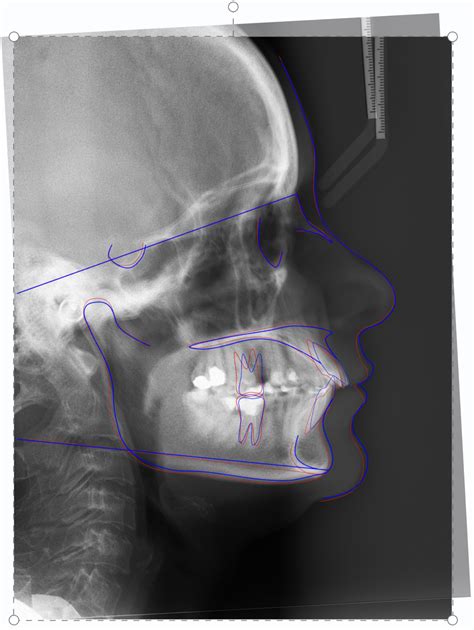

3D Imaging

Three-dimensional (3D) imaging techniques, such as cone-beam computed tomography (CBCT), provide a more comprehensive view of the craniofacial structures. These images allow orthodontists to assess the patient’s dental and skeletal relationships from multiple angles, enhancing diagnostic accuracy and treatment planning.

Software Analysis

Advanced software programs are now available to assist in the analysis of Cephalometric X Rays. These programs can automatically identify landmarks and measurements, reducing the potential for human error and improving the efficiency of the diagnostic process.